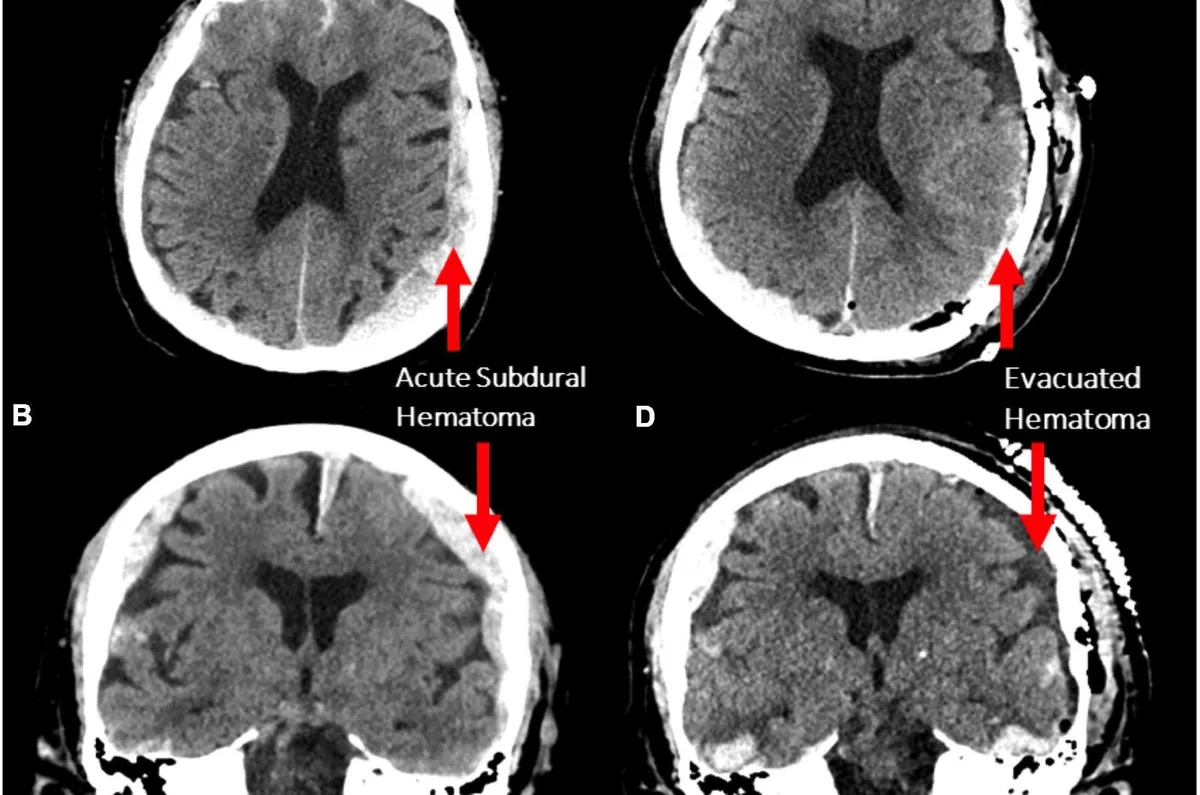

Fotó: Frontiers of Ageing in Neuroscience